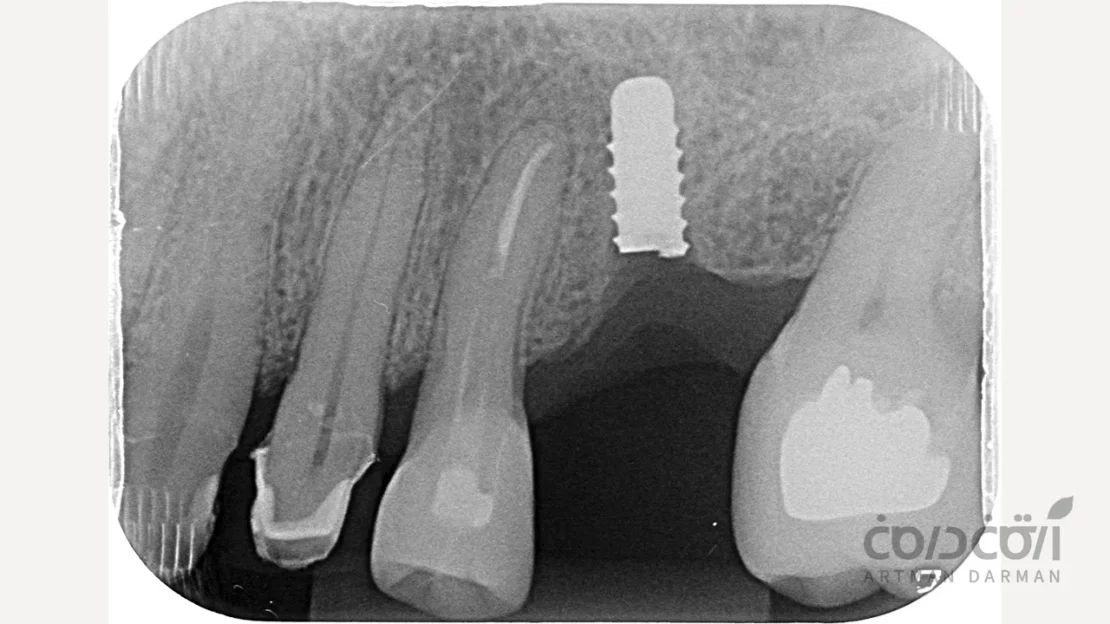

- معاینه بالینی: بررسی لقی غیرطبیعی پروتز.

- تهیه رادیوگرافی (X-ray): این مهم ترین ابزار تشخیصی است. در رادیوگرافی، یک خط شکست واضح در بدنه ایمپلنت قابل مشاهده است. گاهی برای بررسی دقیق تر، از اسکن سه بعدی (CBCT) استفاده می شود.